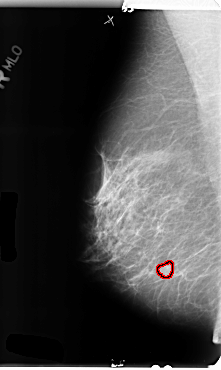

B_3146_1.RIGHT_MLO

RIGHT_MLO LINES 4800 PIXELS_PER_LINE 2872 BITS_PER_PIXEL 12 RESOLUTION 50 OVERLAY

FILE: B_3146_1.RIGHT_MLO.OVERLAY

TOTAL_ABNORMALITIES 1

ABNORMALITY 1

LESION_TYPE MASS SHAPE IRREGULAR MARGINS MICROLOBULATED-ILL_DEFINED

ASSESSMENT 4

SUBTLETY 3

PATHOLOGY BENIGN

TOTAL_OUTLINES 1

BOUNDARY